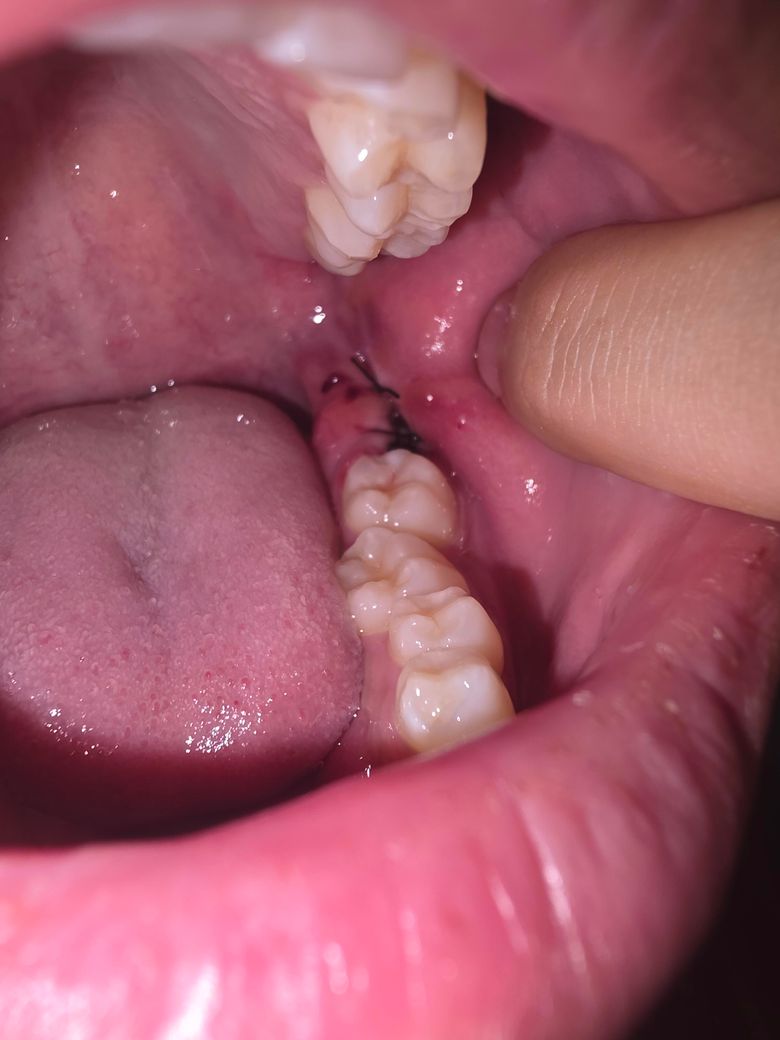

어제 오후에 왼쪽 사랑니를 뽑았습니다

어제 저녁에 샤워하다가 피떡이 떨어졌는지 피가 났었고 거즈로 어찌저찌 지혈해서 지금은 피가 나지는 않습니다만 피떡이 거의 없다시피한 상황이네요 혹시 문제가 있다거나 그런건 아닌거죠...?

• 1번 째 사진

1. 발치 후 혈병은 24~48시간 내 사라지면서 잇몸 치유를 위한 세포가 형성됩니다.

2. 발치 후 부종, 붓기는 당연히 있을 수 있습니다. 얼음찜질 해주세요